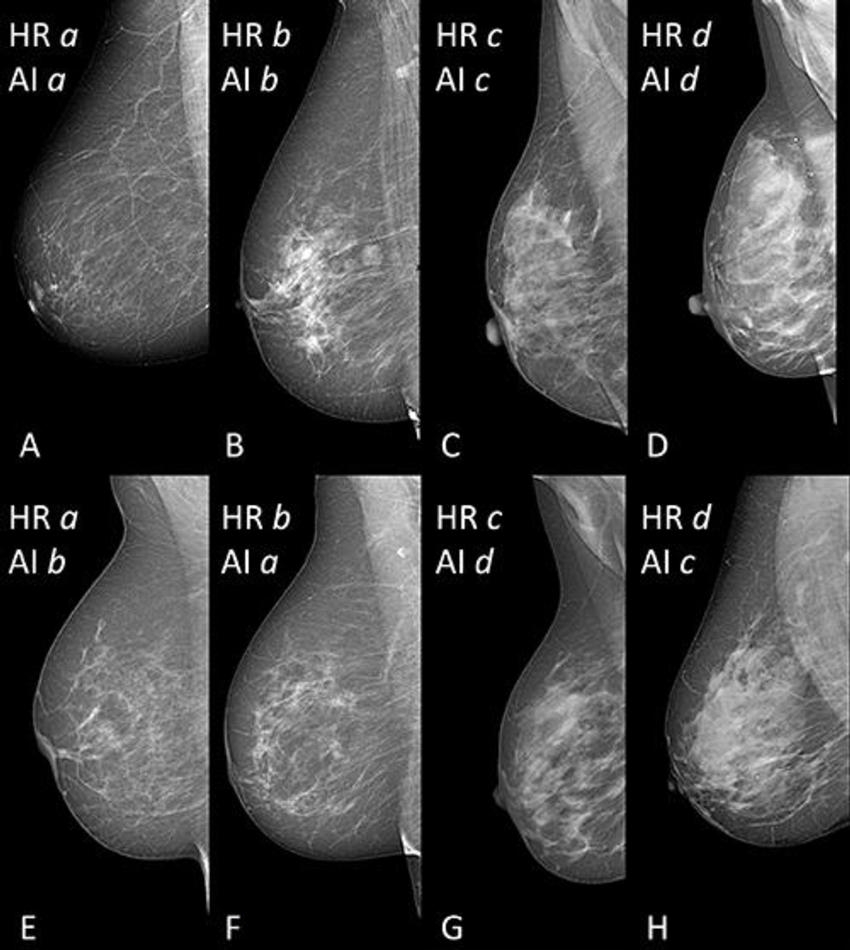

Figure 1. Selection of mammographic mediolateral oblique views of breasts with different breast density from women between 51 and 68 years of age. (A–D) Examples of human readers (HR)-(AI) agreement for category a (68 years), b (66 years), c (51 years), and d (54 years); B shows an example of a breast with a benign mass. (E–H) Examples of HR-AI disagreement; E was classified as a by HR, and as b by AI (67 years); F was classified as b by HR, and as a by AI (68 years); G was classified as c by HR, and as d by AI (55 years); H was classified as d by HR, and as c by AI (52 years). Note - Breast Imaging Reporting and Data System (BI-RADS): category a (almost entirely fatty), category b (scattered fibroglandular), category c (heterogeneously dense), category d (extremely dense).